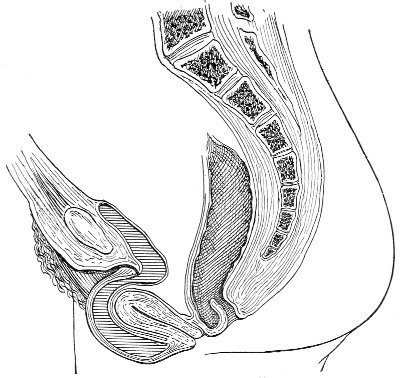

An accurate knowledge of the anatomy and mechanism of the female perineum is essential to an understanding of the nature and treatment of injuries to this structure. The anatomical structures lying between the anus behind and the symphysis pubis in front are those that most directly interest the gynecologist. Proceeding from 57 below upward, we find the following structures lying in superimposed planes: the skin, the superficial fascia, the deep layer of the superficial fascia, the transversus perinæi and the sphincter vaginæ muscles, the anterior layer of the triangular ligament, the posterior layer of the triangular ligament, the levator ani muscle (Fig. 19).

Fig. 18, A.—Superficial structures of the female perineum (Weisse).

The vagina passes through these structures. They surround and support the ostium vaginæ as the fascia and muscles surround and support the opening of the rectum or the anus. The muscles and fasciæ are attached in the median line between the anus and the vagina, and therefore this part of the body, which is called the perineum, is supported or maintained in its 58 proper position by these various structures. The transversus perinæi arises from the ramus of the ischium and is inserted in the perineum. The bulbo-cavernosus, or sphincter vaginæ, arises in the perineum and is inserted in and about the clitoris. The inner fibers of the levator ani arise from the symphysis pubis and are inserted in the perineum and the lower part of the vagina (Fig. 20). When these muscles contract, their action, therefore, is to draw the perineum upward and forward. At the same time the anus is drawn upward and forward, and so also is the posterior margin of the ostium vaginæ and the lower portion of the posterior vaginal wall.

The vagina has no circular sphincter like the anus, but 59 the vaginal month is kept closed by the action of the transversus perinæi, sphincter vaginæ, and levator ani muscles, which draw the perineum forward, and thus keep the posterior vaginal wall in apposition with the anterior wall.

This sling of muscles and fascia, which surrounds and supports the opening of the vagina, may readily be felt in the nulliparous woman by introducing the finger in the vagina and pressing backward and outward toward the ischio-rectal fossa. We then feel plainly, immediately within the ostium vaginæ, a firm resisting band of tissue, apparently about half an inch broad, embracing the posterior portion of the lower vagina. This band is formed by the inner edges of the various muscles and planes of fascia that have been described.